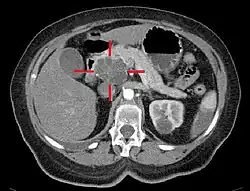

Medical imaging techniques, such as computed tomography (CT scan) and endoscopic ultrasound (EUS) are used both to confirm the diagnosis and to help decide whether the tumor can be surgically removed (its "resectability").[12] On contrast CT scan, pancreatic cancer typically shows a gradually increasing radiocontrast uptake, rather than a fast washout as seen in a normal pancreas or a delayed washout as seen in chronic pancreatitis.[66] Magnetic resonance imaging and positron emission tomography may also be used,[2] and magnetic resonance cholangiopancreatography may be useful in some cases.[40] Abdominal ultrasound is less sensitive and will miss small tumors, but can identify cancers that have spread to the liver and build-up of fluid in the peritoneal cavity (ascites).[12] It may be used for a quick and cheap first examination before other techniques.[67]

.jpg)